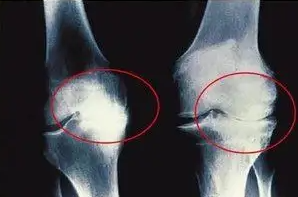

관절염이란 말 그대로 관절에 염증이 생긴것을 말합니다. 염증으로 인해 관절을 움직일때마다 통증이 생길 수 밖에 없습니다. 평소에 좋은 습관과 운동 그리고 식단 관리로 관절염 예방 해보시기 바랍니다.